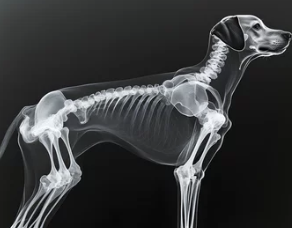

1. 강아지 허리디스크란?

강아지 허리디스크(추간판 탈출증)는 척추 뼈 사이의 디스크(연골 조직)가 탈출하여 신경을 압박하는 질환이다.